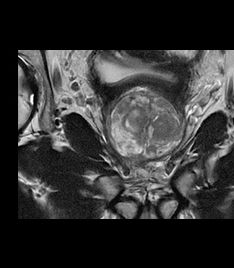

DL-based 3D and motion-insensitive reconstruction advances multiparametric MR prostate imaging

radiomed explores the advantages of using the recently expanded capabilities of AIR™ Recon DL for multiparametric prostate MR (mpMRI) exams.